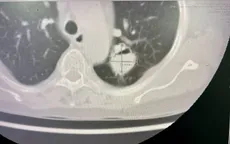

Ho ra máu tái diễn vì khối u nấm phổi

VTV.vn - Bệnh viện Đa khoa tỉnh Quảng Ninh vừa thực hiện thành công ca cắt thùy phổi cho bệnh nhân nữ 65 tuổi mắc u nấm phổi phức tạp, chấm dứt tình trạng ho ra máu kéo dài.